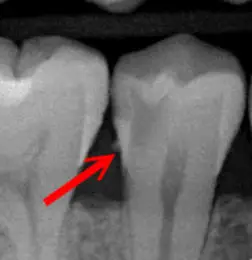

Für eine zuverlässige Kariesfrüherkennung sind bildgebende Verfahren in der Zahnmedizin sehr hilfreich. Gerade Karies in den Zwischenräumen wird mit bloßem Auge häufig erst in einem fortgeschrittenen Stadium sichtbar.

Die Zahnstrukturen werden dabei detailliert abgebildet; kariöse Bereiche können als klar abgegrenzte, dunkler erscheinende Areale sichtbar werden. So lassen sich zum Beispiel Approximal- (Zwischenraum-) und Okklusalkaries (Kauflächenkaries) häufig frühzeitig erkennen.